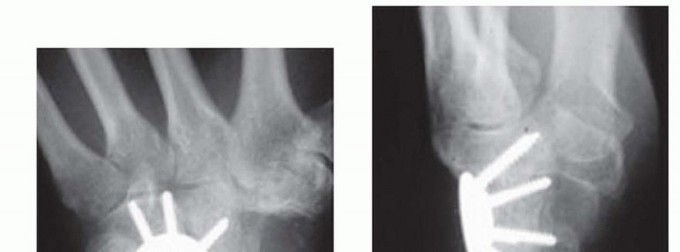

RADIOCARPAL (RADIOLUNATE) ARTHRODESIS

TECH FIG 6 • A,B. Preoperative AP and lateral radiographs. C,D. Postoperative AP and lateral radiographs following radiocarpal arthrodesis. Under fluoroscopy, correct any preoperative VISI or DISI deformity.A Kirschner wire inserted into the dorsal lunate may be used as a joystick to effect correction.Stabilize the lunate in the reduced position with provisional Kirschner wires from the radius into the lunate.Harvest bone graft from the distal radius or iliac crest and pack the graft tightly into the palmar radiolunate joint.Secure the lunate to the radius with Kirschner wires, headless screws, staples, or small blade plates. Pack the remaining bone graft into the dorsal radiolunate joint.Perform a routine closure and apply a splint.The previously described technique is taken from published data.14,278. Capitolunate ArthrodesisMake a dorsal incision from base of second metacarpal to Lister tubercle.Use the third and fourth extensor interval as described earlier.Perform an inverted “T” capsulotomy to visualize the scapholunate and capitolunate joints. Perform a limited styloidectomy (˜3mm) and excise the proximal pole of scaphoid.Stabilize distal scaphoid to capitate with a Kirschner wire. Alternatively, the entire scaphoid can be excised.Denude the capitolunate articulation.Harvest bone graft from distal radius or iliac crest and pack it into this prepared joint.Tricortical iliac crest graft allows maintenance of carpal height.Assure capitolunate alignment with a Kirschner wire as described earlier for CHLT fusion.Place a guidewire followed by headless screw into proximal ulnar corner of lunate as described earlier for CHLT fusion.Take wrist through a range of motion to be certain a mechanical block is not present. Perform a standard closure and apply a splint.The previously described technique is taken from published data.12,15P.989